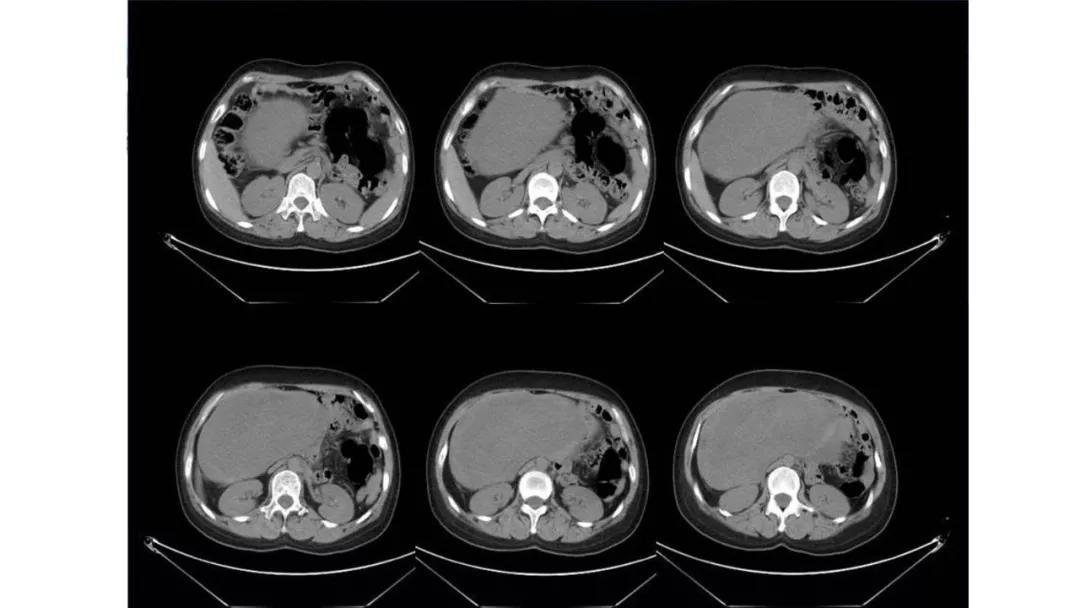

病理:浆液性囊腺癌

病理:颗粒细胞瘤

病理:子宫肌瘤粘液样变性